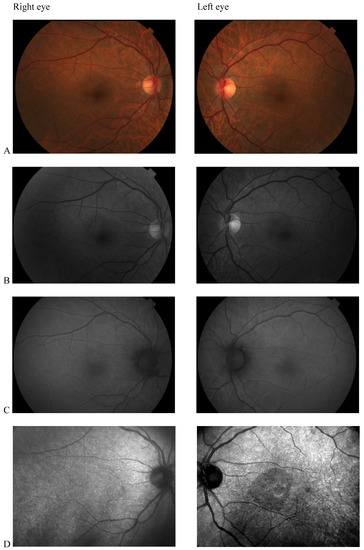

Color fundus photography, red-free fundus photography, fundus autofluorescence, and fluorescein angiography were normal in both eyes. The abnormal macular reflex in the left eye was evident only on a scanning laser ophthalmoscopy (SLO) infrared fundus image obtained with optical coherence tomography (OCT) (OCT/SLO NidekRS-3000 ADVANCE) (Figure 1). OCT scans revealed a reduction of perifoveal macular thickness, which was greater in the left eye (Figure 2A). Retinal layers segmentation analysis showed a marked reduction of the outer nuclear layer (ONL) in the perifoveal region of the left eye (Figure 2B). Humphrey perimetric 30–2 threshold test showed a central scotoma in the left eye (Figure 2C). A multifocal electroretinogram showed blunted foveal peak in the left eye. The voltage of the first positive wave (P1) was decreased in the temporal macula (Figure 2D). Fluorescein angiography was normal in both eyes (Figure 2E).

Figure 1. (A) Color fundus photography; (B) red-free fundus photography; (C) fundus autofluorescence; (D) Scanning laser ophthalmoscopy (SLO) fundus image revealed abnormal macular reflectivity in the left eye.